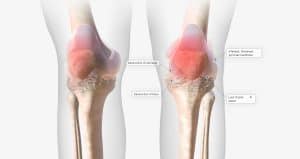

While there is no single definitive test to diagnose knee OA, doctors typically use a combination of methods. They will ask you about your symptoms, perform a physical examination, and may order imaging tests such as X-rays or MRI scans. They may also perform blood tests to rule out other conditions that could be causing your symptoms.

At RMRM, we want to help you heal your arthritic joint, repair cartilage defects, regenerate the tissue that has been damaged, and help you get back to the things you love with those who matter most. The most robust treatment we offer to treat knee OA is Stem Cell Therapy. This therapy involves harvesting your own stem cells from your adipose (fat) cells, processing them, and injecting them into the joint.

Stem cells have been shown by research and our real life clients to repair damaged joint tissue, cartilage defects, reduce inflammation, and regenerate damaged cartilage. Stem cells secrete growth factors that promote tissue repair, regeneration, and decrease inflammation. By injecting stem cells into the joint, it is possible to stimulate the body’s natural repair mechanisms and promote healing.